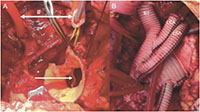

The operative aims for this complex patient were the following: replacing remainder ½ of the ascending aorta, repair of remaining pseudoaneurysm perfusing the posterior Bentall graft (Figure 1C), total arch replacement, and exclusion of false lumen in descending thoracic aorta. It was clear that this operation had to obviate further sternotomies. Therefore, a two-stage hybrid procedure was planned with an open surgical part replacing the ascending and transverse aorta and an endovascular approach to complete the elephant trunk in the descending thoracic aorta. The patient had uneventful forth redo-sternotomy and extensive lysis of adhesions. Deep hypothermic circulatory arrest was initiated with antegrade cerebral perfusion through right axillary artery perfusion. The aortic arch was opened and resected. The left carotid artery was used for bilateral antegrade cerebral perfusion, while the left subclavian artery was clamped to reduce steal phenomenon (Figure 4A). The elephant trunk cuff was placed in the proximal descending aorta after a generous surgical fenestration of the septum. Using a 30mm Dacron graft, the distal aortic anastomosis was performed about a cm distal to left subclavian artery and perfusion to lower extremity was initiated through a second arterial cannula and a side-branch. While rewarming the patient, a trifurcated graft was anastomosed to all brachiocephalic vessels (Figure 4B). The ascending pseudoaneurysm was repaired by cutting out the old Dacron graft down to neo-sinotubular junction. Next the trifucated graft was anastomosed to the ascending aorta and the patient was weaned uneventfully off the heart-lung machine. The circulatory arrest time to lower body was 52 minutes, while the operative time was eight hours. The patient was extubated, neurologically intact, next day in the intensive care unit. His postoperative course was complicated by hospital-acquired pneumonia and C. difficile colitis. Due to infection risk, it was decided not to perform the endovascular stage in the same hospital stay, therefore six weeks after his initial operation, he returned for the TEVAR.

Figure 4: Intraoperative Image. A: Operative situs after arch resection with antegrade cerebral perfusion (#). Opened descending aorta with dissection membrane (*). B: After trifurcated vascular graft implantation (BT: brachiocephalic trunk, LCA: left coronary artery, LSA: left subclavian artery).